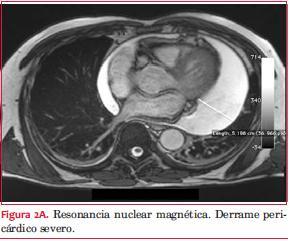

Resonancia nuclear magnética: derrame pericárdico severo. Pericardio normal. Tumor intrapericárdico de 36 por 32 mm, sólido, hipervascularizado, bien delimitado, con centro necrótico (figuras 2A, B y C).